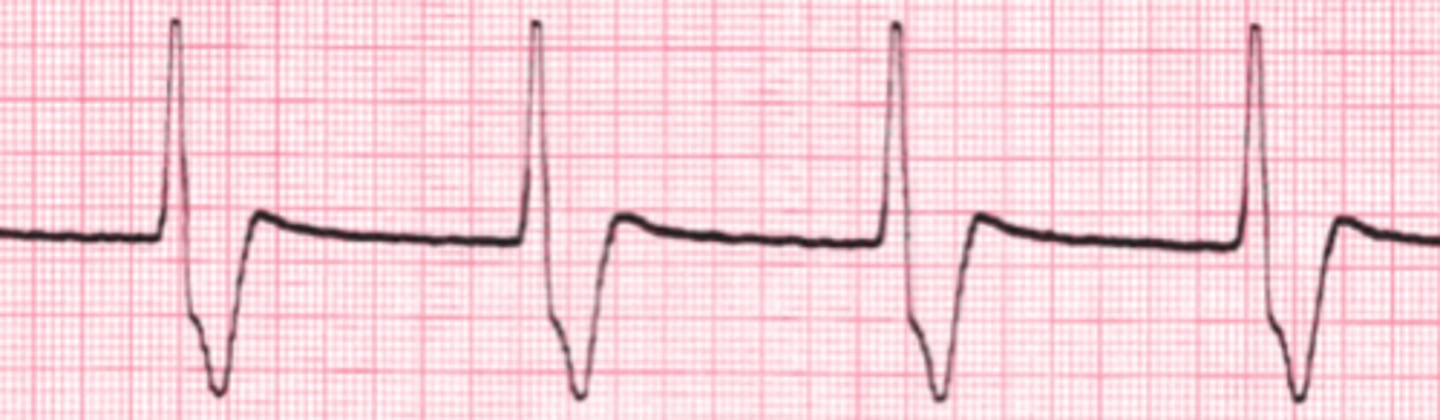

Normal Sinus

Name the rhythm